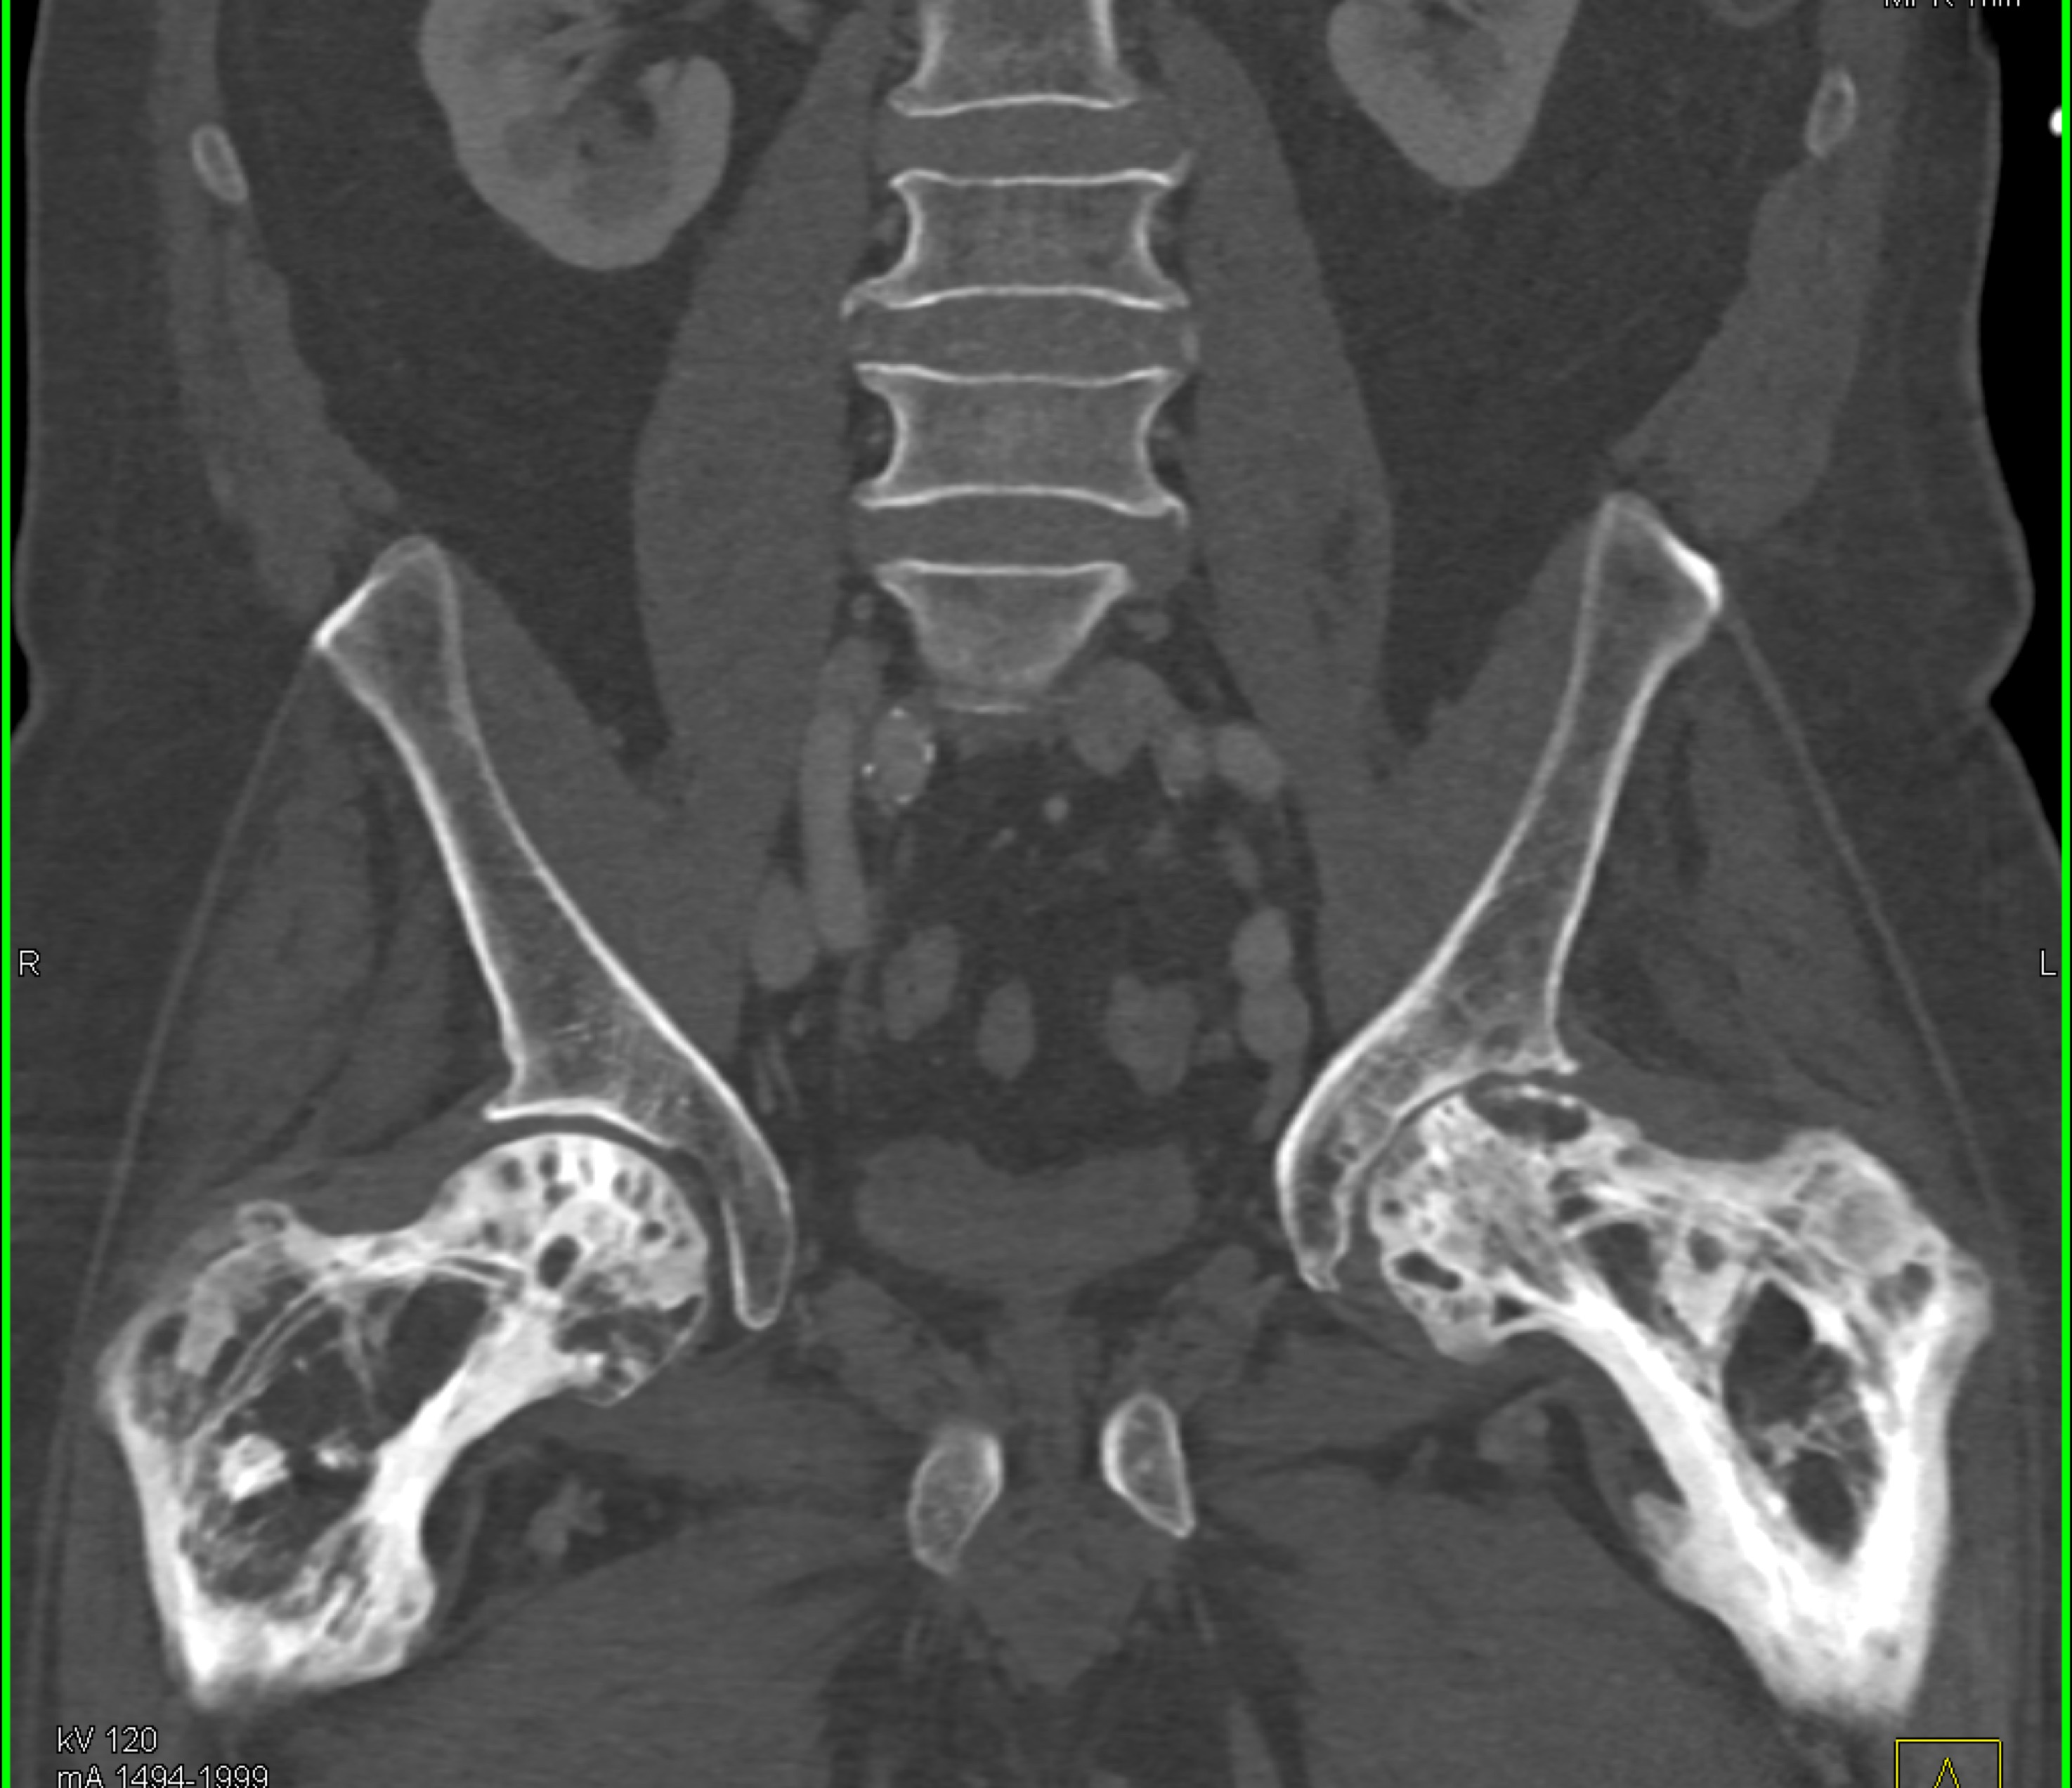

9) The best diagnosis in this 30ish year old female is?

renal cell carcinoma

MEST tumor (mixed epithelial and stromal tumor)

Wilms tumor

polycystic kidney disease